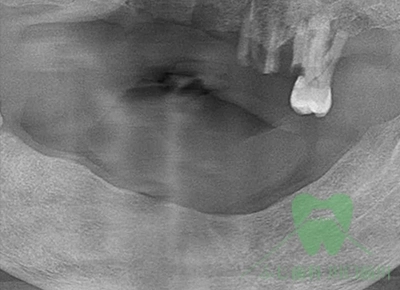

症例1 臼歯部インプラント治療の症例

レントゲン

インプラントの症例1の術前の写真

術前

インプラントの症例1の術後の写真

術後